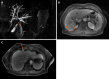

Case summary: A 70-year-old woman was referred to our center due to progressive fatigue, weight loss, abdominal pain, night sweats, and elevated liver enzymes. Magnetic resonance cholangiopancreatography and endoscopic retrograde cholangiopancreatography (ERCP) revealed proximal common hepatic duct and hilar biliary strictures extending bilaterally to lobular bile ducts. Although initial clinical, endoscopic and radiological signs were typical for hilar cholangiocarcinoma, histological examination showed no signs of malignancy. In total, 8 biopsies using different approaches were performed (several biopsies from dominant stricture during ERCP and direct cholangioscopy; ultrasound-guided liver biopsy; diagnostic laparoscopy with liver and lymph node biopsies). Histological examination revealed signs of IMT, and the final diagnosis of biliary IMT was stated. Although IMT is usually a benign disease, in our case, it was complicated. All pharmacological treatment measures were ineffective. The patient still needs permanent stenting, suffers from recurrent infections and mechanical jaundice. Despite that, the patient already survived 24 mo.